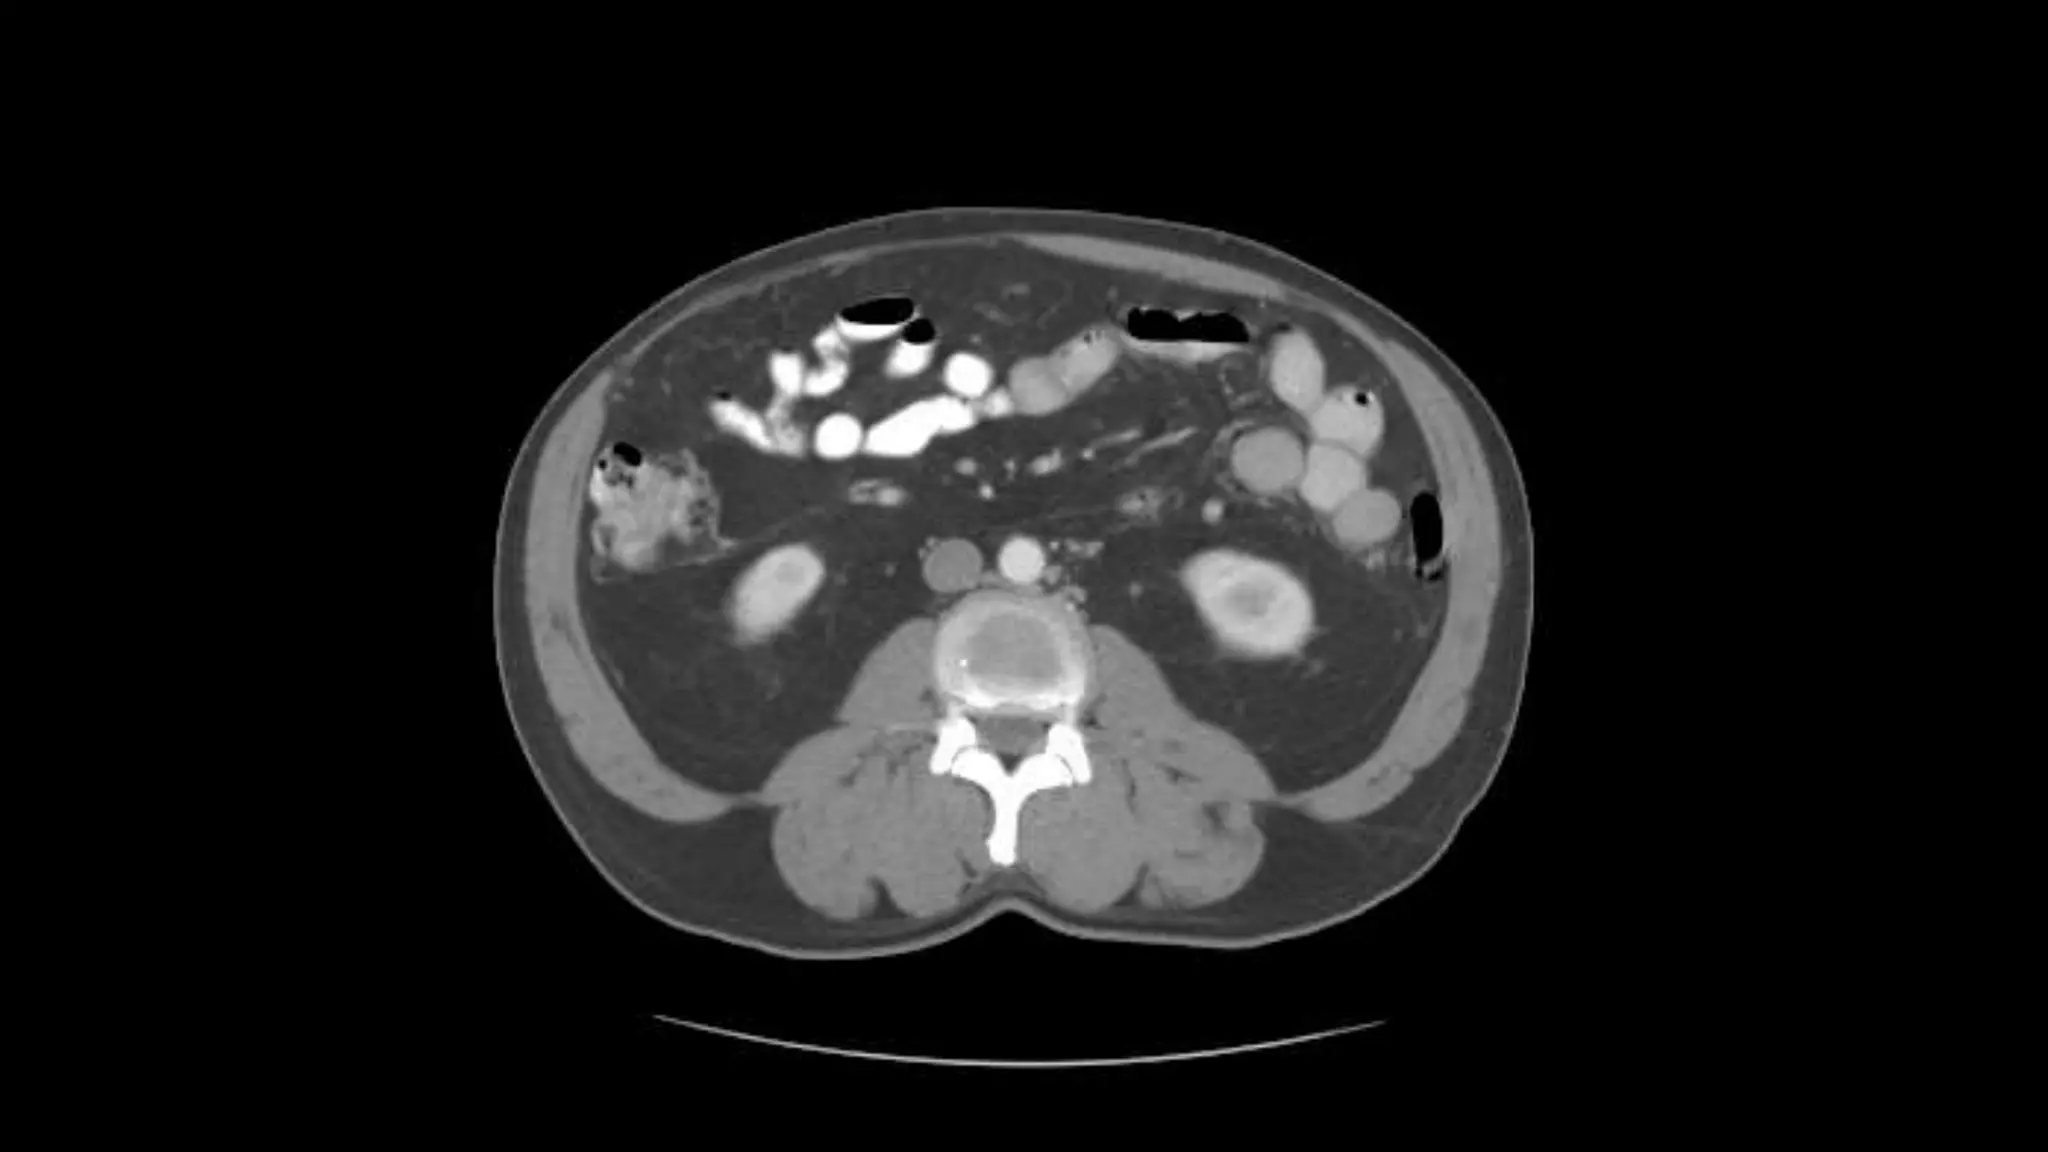

This is the Superior Mesenteric Artery branching

off the Aorta.

Rt. and Lt.Kidneys

Pancreas

Renal Veins emptying into the IVC. We also see the right renal artery branching

off the Aorta, follow it down till you see it enter the right kidney. The Superior

Mesenteric Vein is outlined on the top of this image. If you follow the SMV up, you

will see it empty into the Portal Vein.

Here we see the right and left renal vein entering into the Inferior Vena Cava. We

Also see the left renal artery branching off the aorta and heading toward the left

kidney. Page up and down to trace these vessels.

Superior Mesenteric Vein – follow it up as it joins the Splenic

Vein to form the Portal Vein